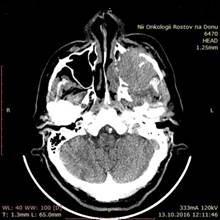

Рак пазух носа

Рак пазух носа 84 фото